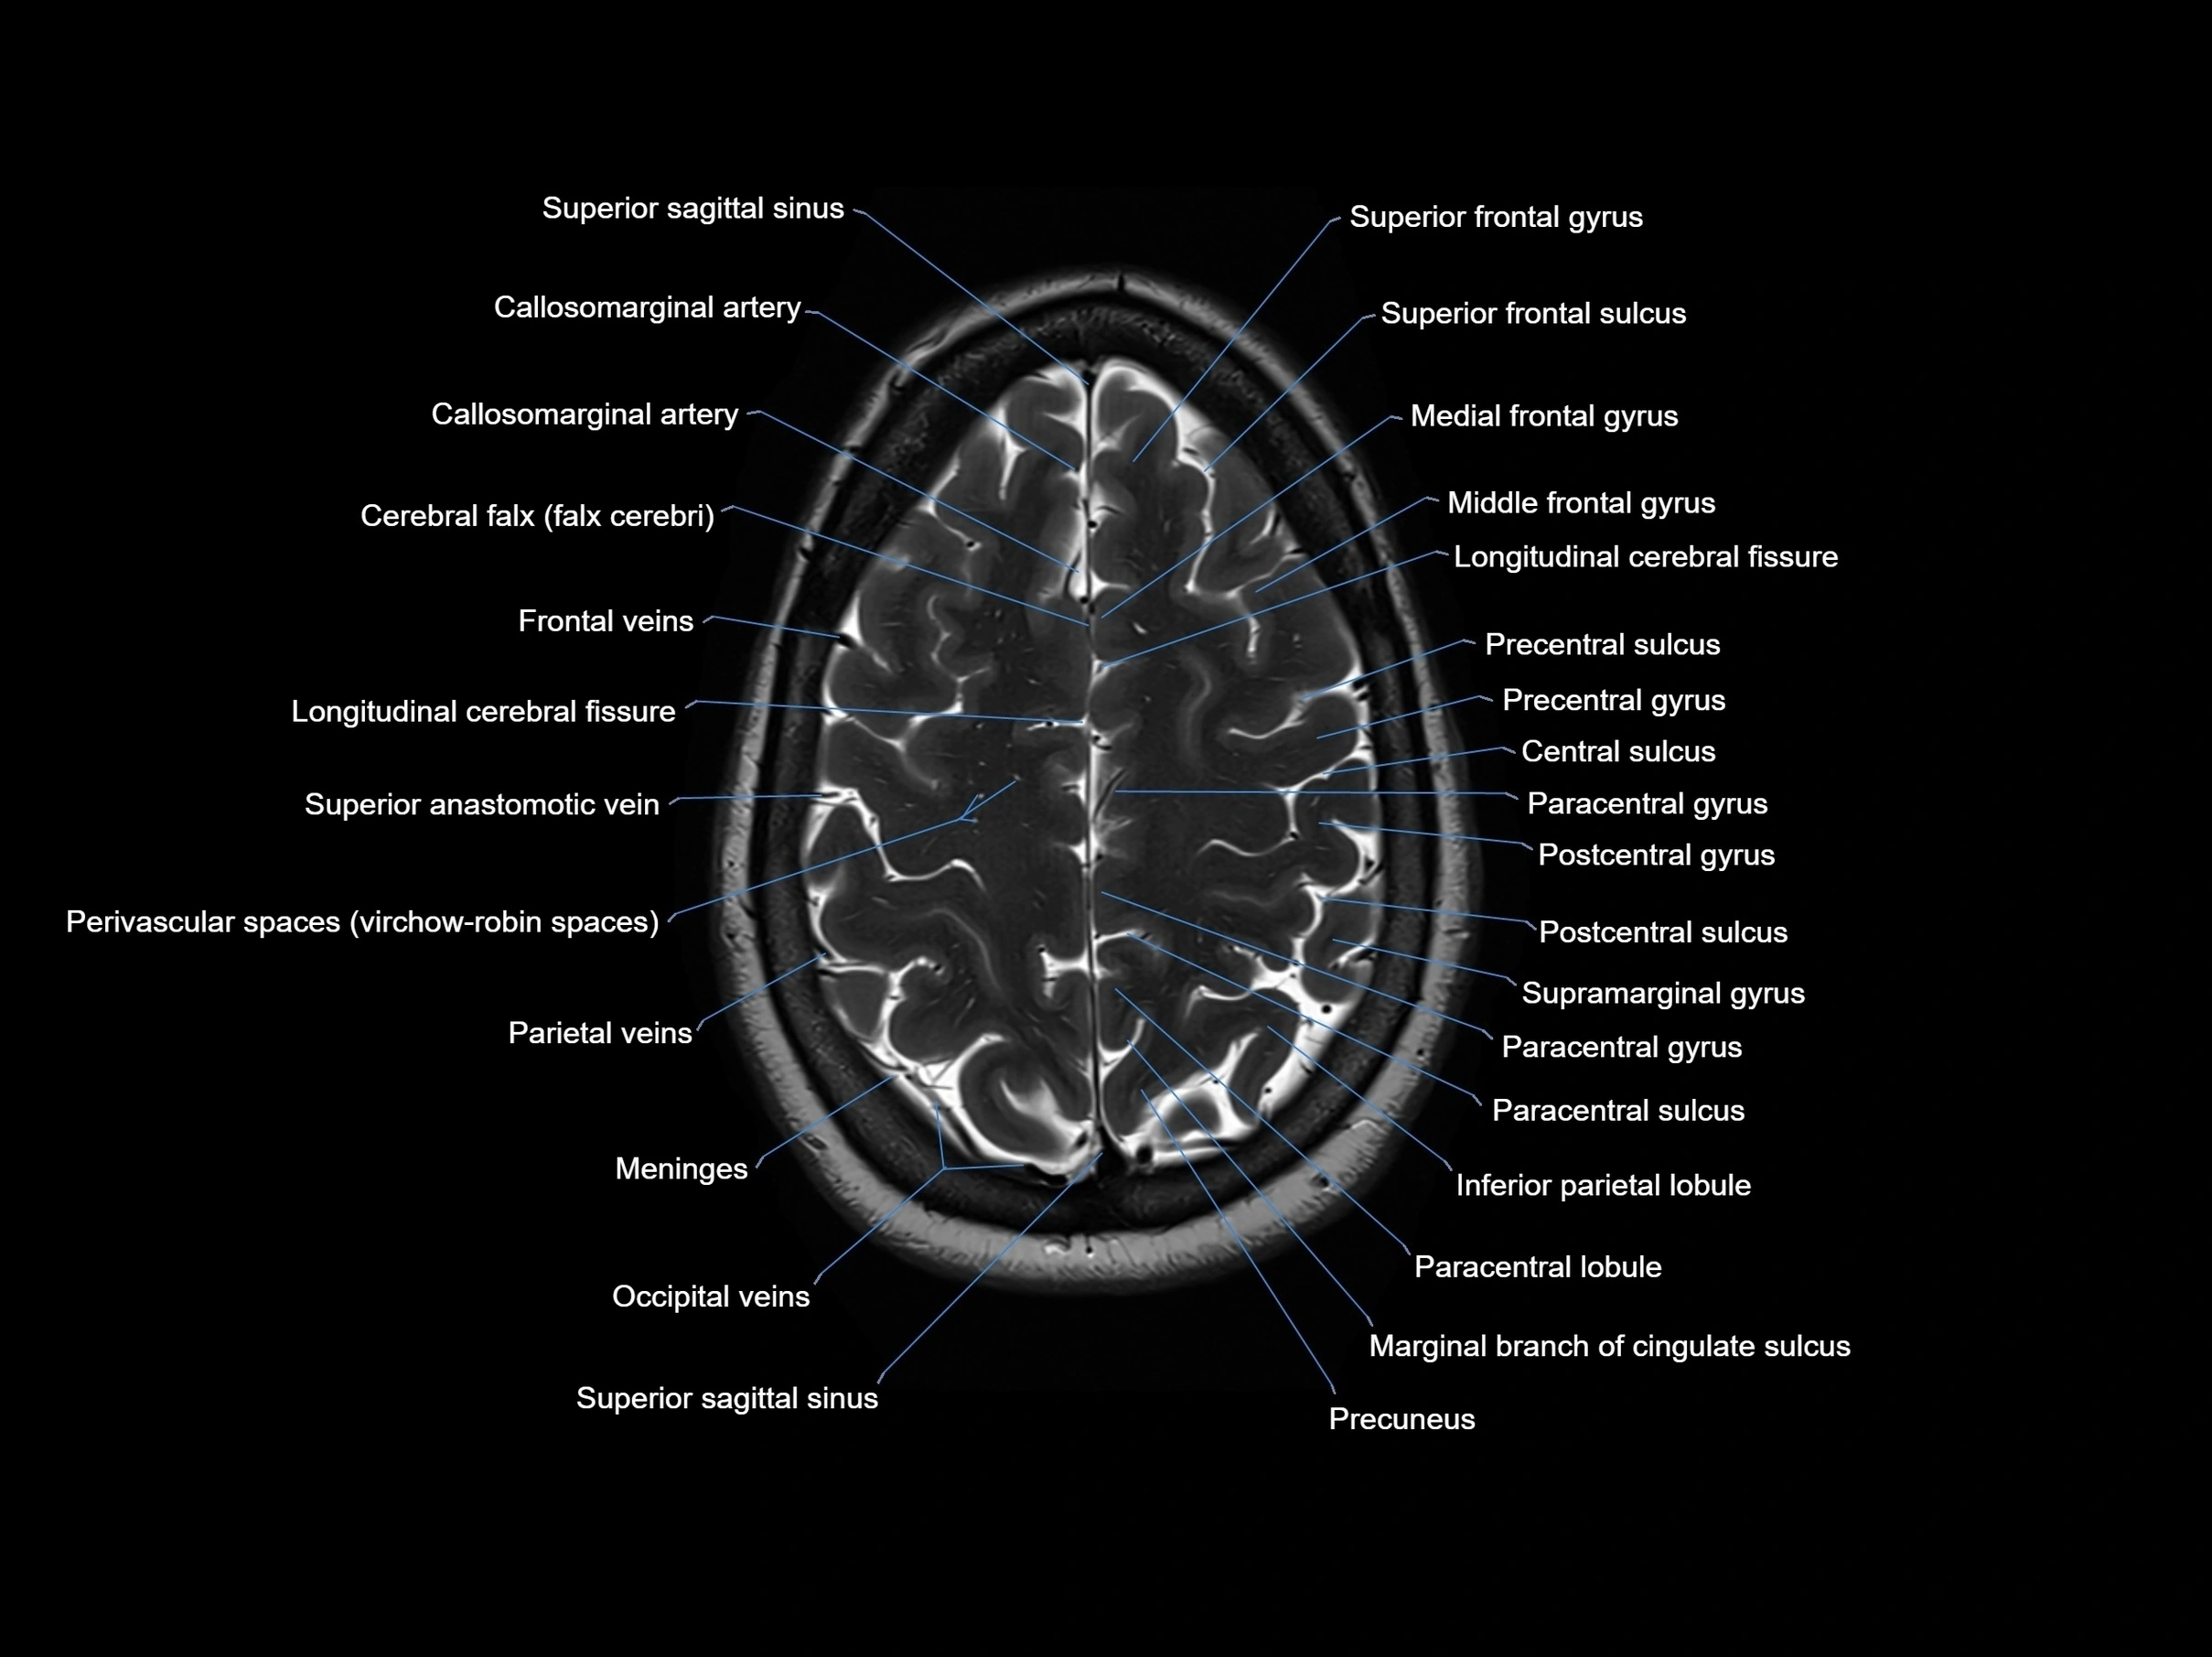

MRI images